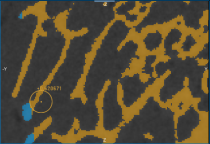

In some cases, an automated segmentation may result in voxels corresponding to trabecular bone erroneously labeled as cortical bone, as circled below, or vice versa.

Automated segmentation result

To edit a segmentation, you can automatically re-assign labeled voxels from one region to interest to another with the Brush tools (see Working with the ROI Painter Tools in 2D Views). In addition, when you work in the Exclusive mode with the Brush tools, only the labeled voxels belonging to the selected regions of interest will be affected when painting.

If you want to re-assign voxels labeled as cortical bone to those labeled as trabecular bone, make sure that the trabecular bone ROI is identified as (A) and that the cortical bone ROI is identified as (B).

- Select the Exclusive option, circled below.

NOTE In this mode, painting will only be applied to the labeled voxels of the selected regions of interest. Unlabeled voxels will not be painted.